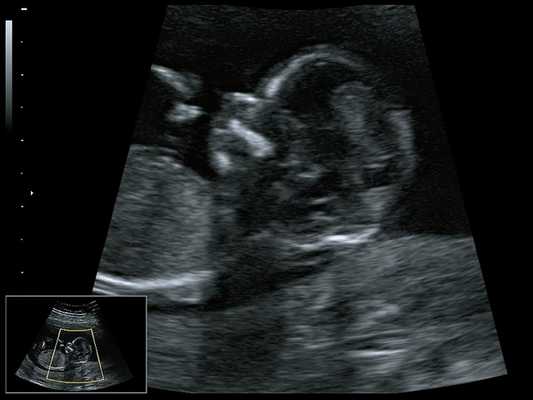

В настоящее время синдром Пьера Робена диагностируется пренатально с помощью скринингового УЗИ в 11-12 недель беременности. После рождения диагноз подтверждается данными клинической картины и инструментальных исследований. Необходимая диагностика:

При ультразвуковом исследовании выявлены множественные особенности лицевого фенотипа у плода: микрогнатия (рис. 2-4), треугольная форма лица (рис. 5), опущенные книзу глазницы и гипоплазия скуловых дуг (рис. 6, 7), аномальная форма и положение ушей (рис. 5, 7).